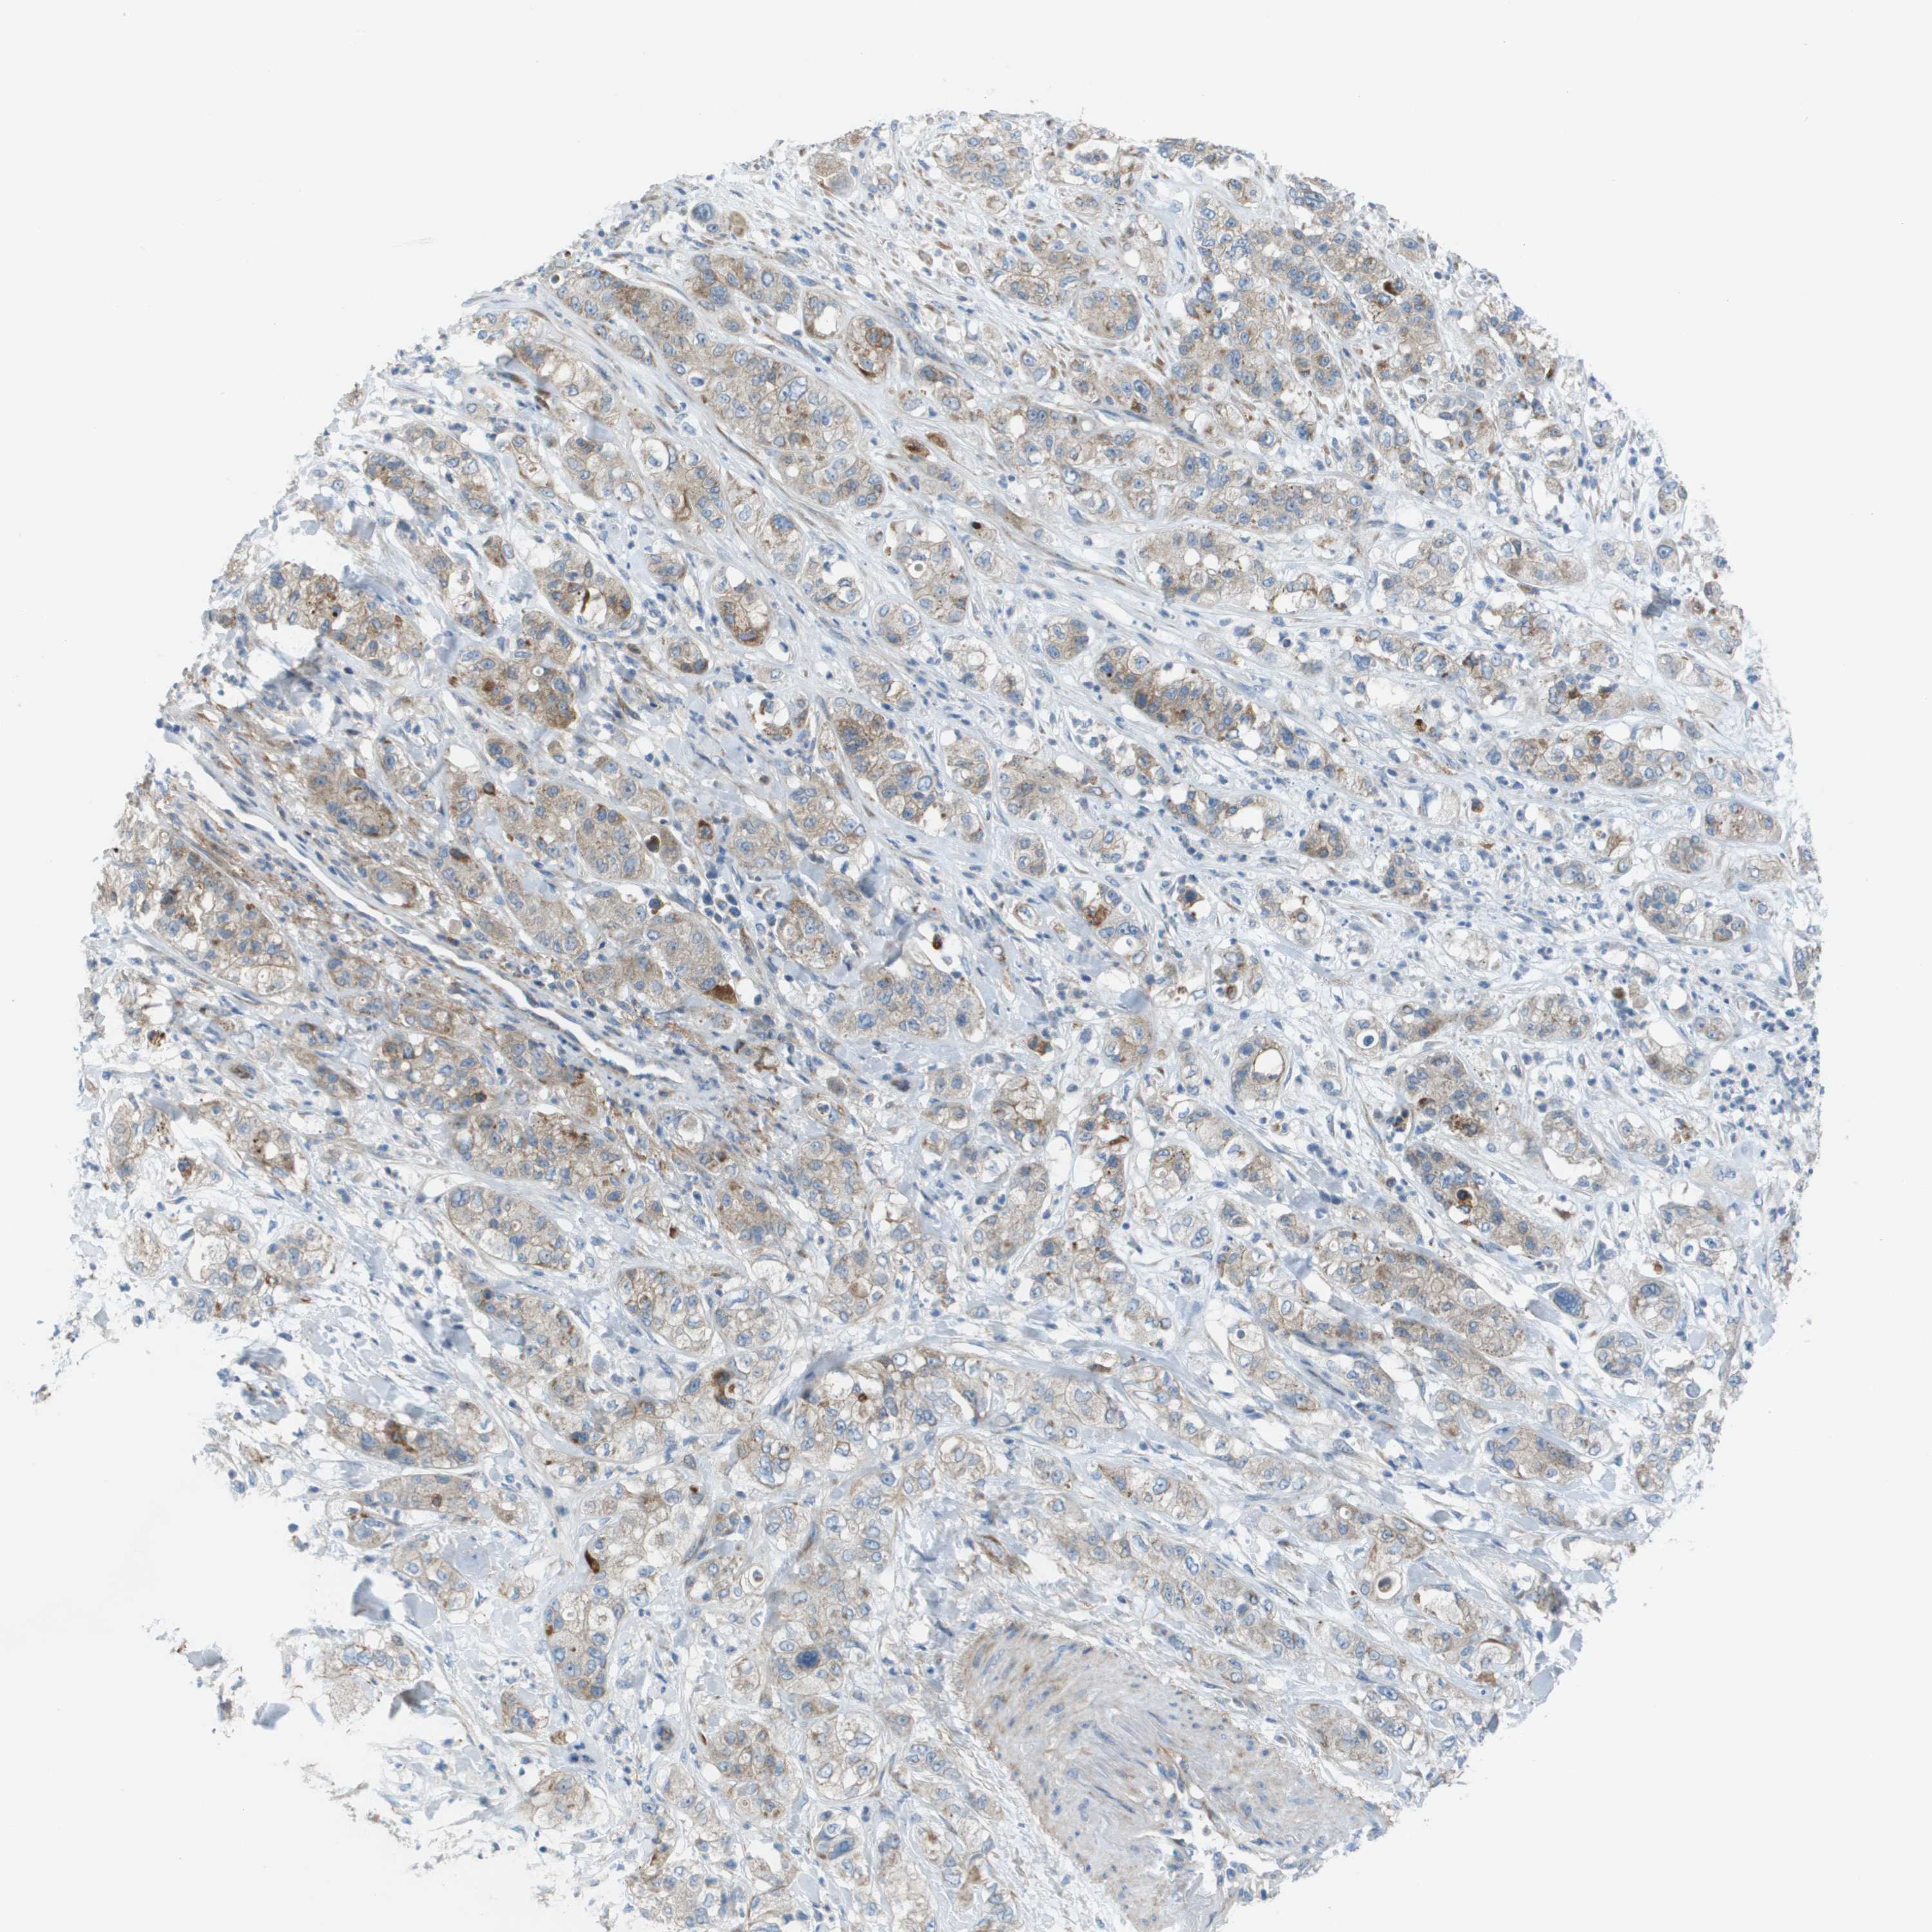

PANCREATIC CANCER - Protein expressioni

A mouse-over function shows sample information and annotation data. Click on an image to view it in a full screen mode. Samples can be filtered based on level of antibody staining by selecting one or several of the following categories: high, medium, low and not detected. The assay and annotation is described here.

Note that samples used for immunohistochemistry by the Human Protein Atlas do not correspond to samples in the TCGA dataset.

Antibody stainingi

Antibody staining in the annotated cell types in the current human tissue is reported as not detected, low, medium, or high, based on conventional immunohistochemistry profiling in selected tissues. This score is based on the combination of the staining intensity and fraction of stained cells.

Each image is clickable and will lead to virtual microscopy that enables deeper exploration of all samples and also displays staining intensity scores, fraction scores and subcellular localization as well as patient and tissue information for each sample.

Antibody HPA011762

Antibody HPA017086

Staining

High

Medium

Low

Not detected

Intensity

Strong

Moderate

Weak

Negative

Quantity

>75%

75%-25%

<25%

None

Location

Nuclear

Cytoplasmic/membranous

Cytoplasmic/membranous,nuclear

Adenocarcinoma, NOS

Adenocarcinoma, metastatic, NOS